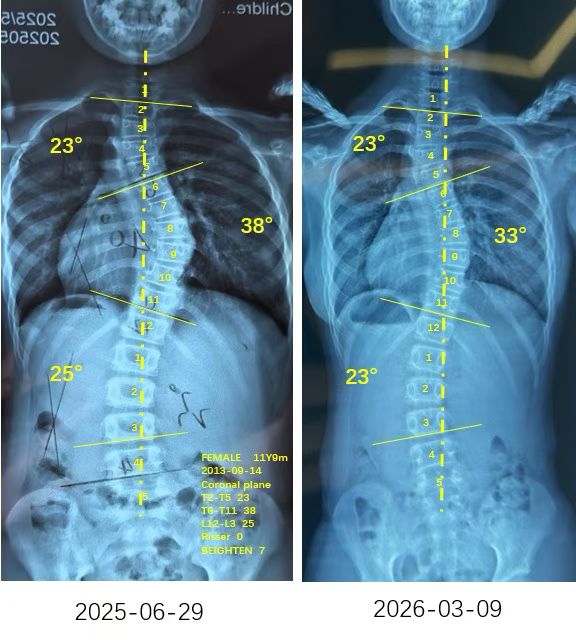

来自家长对衷德的评价(小玉妈妈)

衷德脊柱,我们只关注侧弯保守治疗~